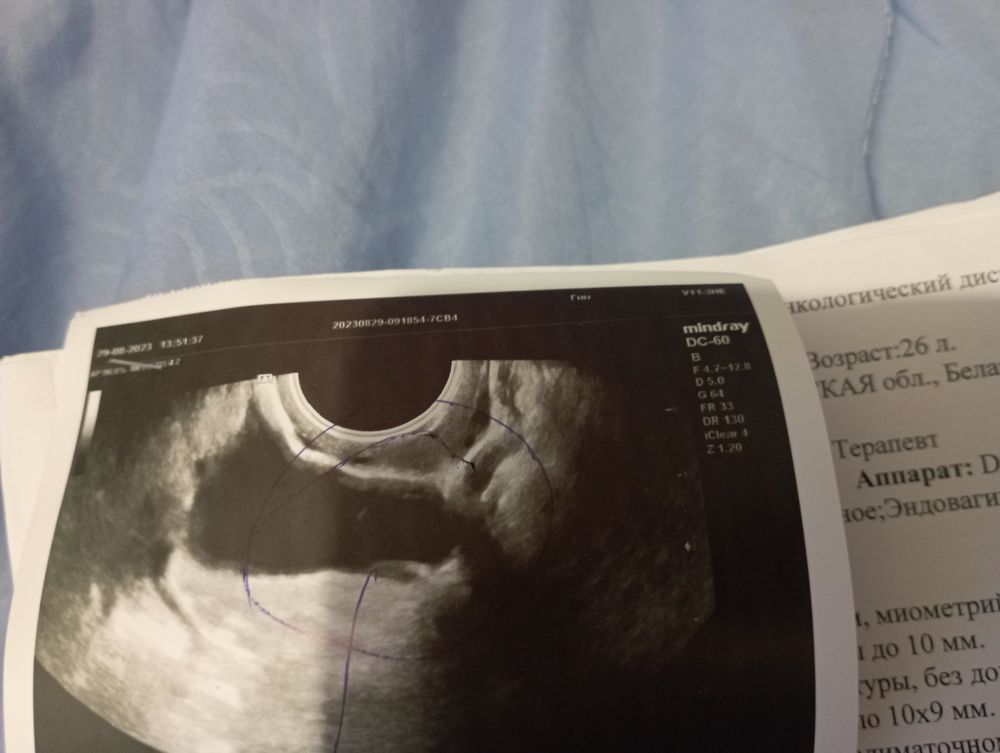

Узи малого таза

Ну не кисты, а киста. Параовариальные кисты не гормонозависимы, как правило ничем не опасны. Так что переживать не о чем

Miss Fisher, в заключении написано кисты на шейки матки еще есть